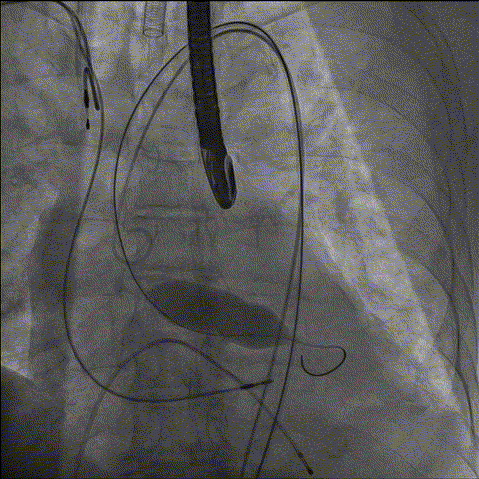

综合各项评估,手术团队采取右侧为主入路,鉴于左冠风险,决定先用10mm球囊,再用22mm球囊预扩,植入Evolut PRO 29mm瓣膜、Cusp Overlap标准6步植入法、20Fr导引鞘。

2、主动脉根部造影